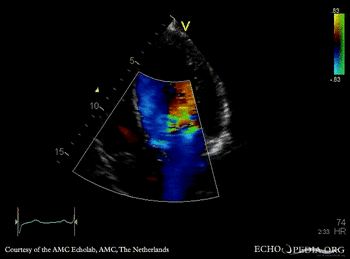

E00444.gif E00445.gif

PLAX: Color Doppler, severe aortic regurgitation A4CH: dilated left ventricle